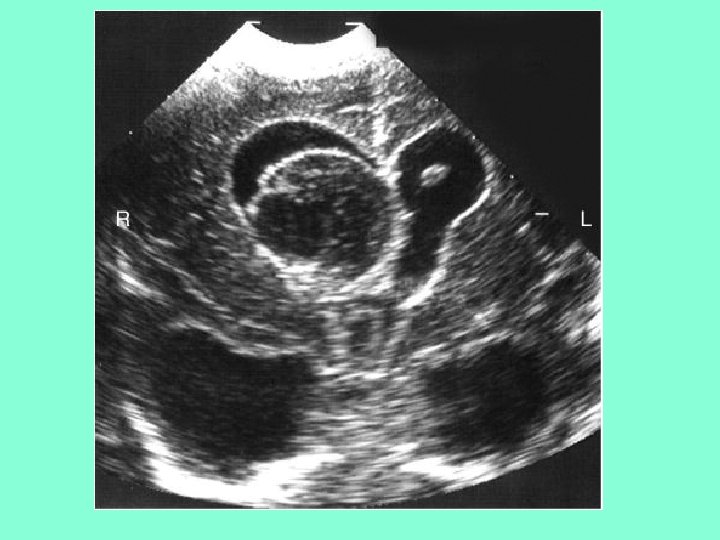

Голопрозэнцефалия с агенезией мозолистого тела

• А – нормальный ребенок в 31 неделю ГВ • В и С - бивентрикулярные кисты